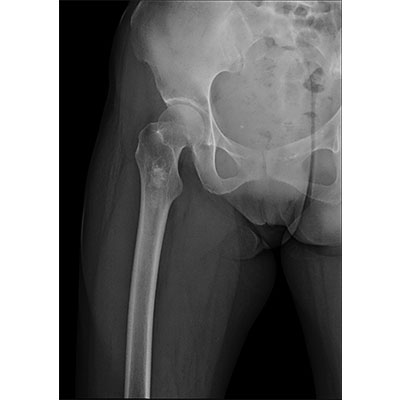

● 采用自主研發(fā)的技術(shù),在保證優(yōu)質(zhì)圖像的前提下,大大降低X射線(xiàn)劑量,用心呵護醫護工作者及患者的健康。

● 短曝光時(shí)間,便于老年人、兒童、殘疾人進(jìn)行臨床拍攝。避免這類(lèi)群體因不能有效控制身體運動(dòng)等因素造成的運動(dòng)偽影,提高攝片質(zhì)量及效率。